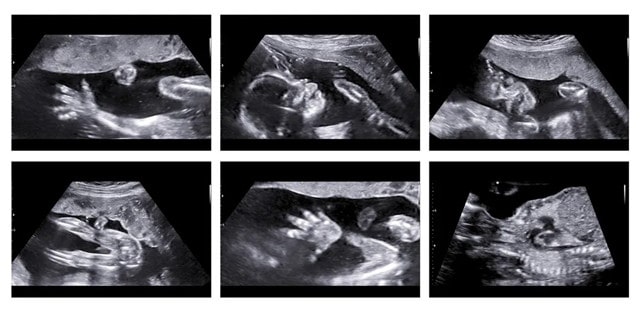

胎动指的是胎儿在子宫腔里的活动冲击到子宫壁的动作。胎儿在子宫内伸手、踢腿、冲击子宫壁,这就是胎动。

一般怀孕满4个月后,即从第5个月开始母体可明显感到胎儿的活动,胎动的次数多少、快慢、强弱等表示胎儿的安危,并不能区分男女。

胎儿在子宫内的胎动大致可以分为4种类型:全身心运动、肢体性运动、下肢运动、胸壁运动。